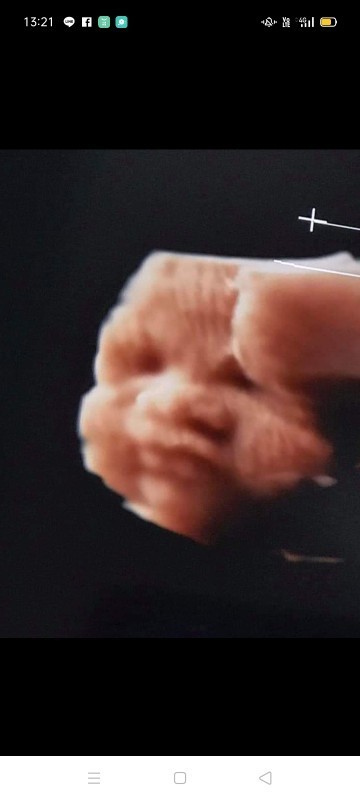

ขอดูรูปภาพอัลตร้าซาวด์ของแม่ๆหน่อยค่ะ